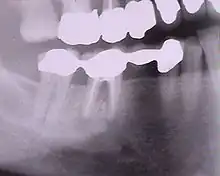

Bridge en place, la gencive n'est pas visible lors du sourire.

Bridge sur modèle en plâtre.